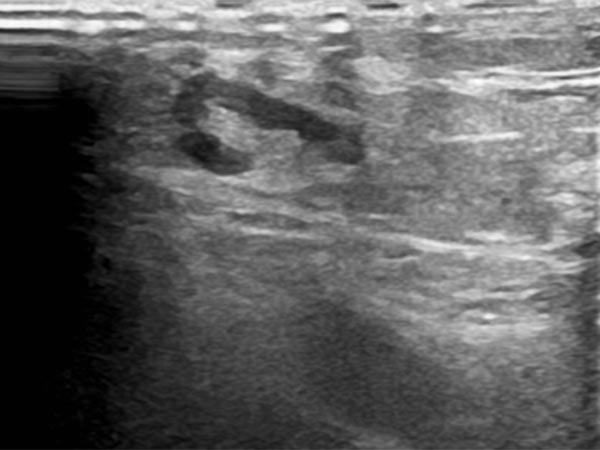

In der B-Bild-Sonographie des subkutanen Anteils der LM zeigt sich ein dysplastisch erweiterter Lymphkanal als echofreie tubuläre Struktur. Das umgebende subkutane Fettgewebe ist deutlich echoreicher als normal durch die eingelagerte Flüssigkeit.

In der B-Bild-Sonographie (Querschnitt proximaler ventraler Oberschenkel) zeigt sich ebenfalls das deutlich echoreiche Gewebe, von einzelnen sehr feinen, dilatierten flüssigkeitsgefüllten Lymphleitern durchsetzt.